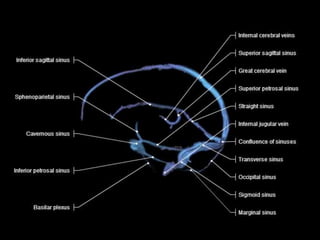

Venous Drainage

Intracranial Veins

There are five types of intracranial veins :

1-Diploic Veins

2-Emissary Veins

3-Meningeal Veins

4-Dural Venous Sinuses

5-Cerebral Veins

4-Dural Venous Sinuses :

-Sinuses are formed within two layers of dura

and drain the veins of the brain , the meninges

and the cranium principally into the internal

jugular vein

-They comprise the following :

1-Superior Sagittal Sinus

2-Inferior Sagittal Sinus

3-Straight Sinus

4-Transverse Sinus

5-Superior Petrosal Sinus

6-Sigmoid Sinus

7-Occipital Sinus and Marginal Sinuses

8-Inferior Petrosal Sinus

9-Sphenoparietal Sinus

10-Cavernous Sinuses